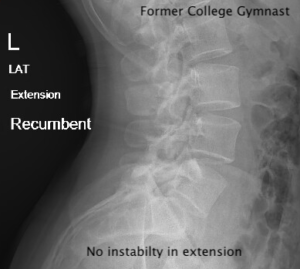

1) For the chiropractor to learn the most common causes, locations, and hallmark x-ray findings of compression fractures and spondylolysis.

II. Spondylolysis